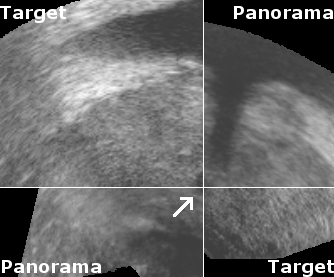

To measure reproducibility and registration success, 10 registrations were carried out for each volume pair from slightly perturbated start points by adding noise of 2mm and 2°. This yielded 10 transformations that approximate the unknown rigid transformation between the prostate in both volumes. The average transformation of the was computed with the method presented in [9]. The euclidean distance error , with being the image center, and the angular error , which corresponds to the rotation angle of , were used to compute the root mean square (r.m.s.) errors and . A registration was considered successful if mm and degrees, and if the result was visually satisfactory when superimposing both volumes in a composite image (See Fig. 2).

Reconstruction accuracy evaluation was more difficult to implement since there is no straight-forward gold standard. In some images, the needle trajectories from previous biopsies were still visible. In these cases, the trajectories were manually segmented, and the angular error between corresponding needle trajectories were used to evaluate rotational accuracy. Also, some patients had significant and clearly visible calcifications inside the prostate. The distances between segmented calcifications were used to determine the translational accuracy. Tab. 1 and Fig. 2 show the results of the evaluations.